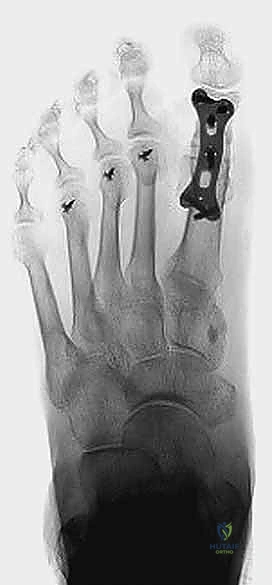

صورة توضيحية لـ جراحة تثبيت مفصل إبهام القدم الكبير المراجعة: استعادة الوظيفة وتخفيف الألم مع الأستاذ الدكتور محمد هطيف

6. التثبيت الدقيق (Rigid Fixation)

بعد وضع العظام في الزاوية التشريحية المثالية (حوالي 10-15 درجة من الانثناء الظهري، و 15 درجة من الانحراف الخارجي)، يجب تثبيتها بقوة هائلة لضمان عدم تحركها حتى تلتئم. يعتمد الدكتور هطيف على أحدث تقنيات التثبيت:

* الشرائح والمسامير (Plates and Screws): استخدام شريحة تيتانيوم مصممة خصيصًا لمفصل إبهام القدم، مع مسمار ضغط (Lag Screw) يمر عبر المفصل لزيادة التلاحم.

صورة شعاعية توضح التثبيت الدقيق لمفصل إبهام القدم الكبير المراجعة باستخدام الشرائح والمسامير الطبية